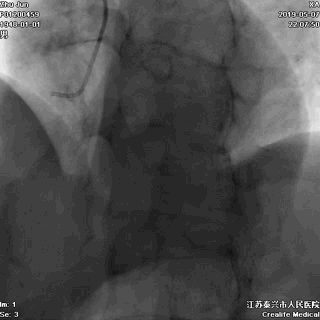

冠脉左主干线样狭窄

回旋支主支中段闭塞

前降支开口次全闭塞

至此,症状、心电图结合冠状动脉造影检查结果,该患者“急性心肌梗死”诊断明确,冠脉造影提示血栓向主干延伸,病情非常危重,死亡风险极大,需要紧急行心脏介入手术。讲明疾病风险和手术风险后,患方很快接受介入手术。